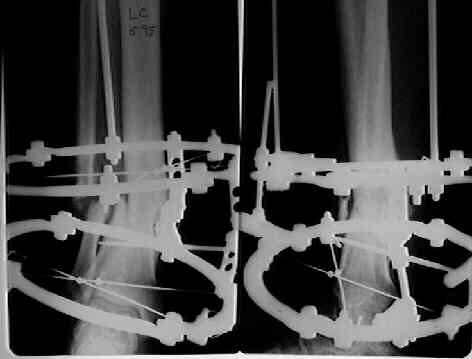

Female. 65 years old. 2 years ago trimalleolar fracture left ankle. First ORIF failed. Second ORIF with autologous graft at the fibular fracture was complicated by infection. The X-ray pictures show the actual situation. What are the suggestions of the group?

Кликните для загрузки файла kjj.jpg

12KB (12815 bytes)